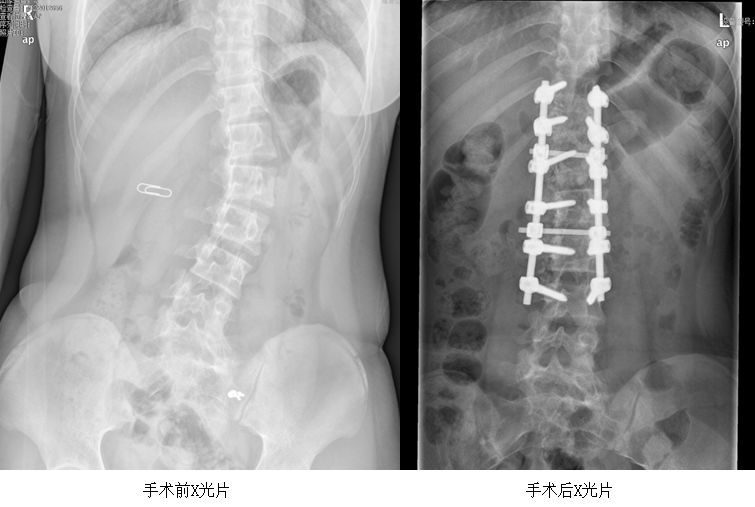

攀鋼總醫(yī)院骨科脊柱外科團隊對小雪的病情進行詳細(xì)評估,她的脊柱側(cè)彎角度超過40°,已達(dá)到手術(shù)標(biāo)準(zhǔn),必須進行手術(shù)矯正。脊柱側(cè)彎矯正手術(shù)堪稱脊柱手術(shù)的天花板,手術(shù)難度很高。小雪患的是青少年特發(fā)性脊柱側(cè)凸 (Lenke 5CN型),如果矯正不夠,隨著發(fā)育成熟,可能會面臨二次手術(shù);若過度矯正,會導(dǎo)致腰椎活動受限加重。

骨科脊柱外科團隊為確保手術(shù)萬無一失,反復(fù)研究病例,制定了一套縝密的手術(shù)方案。充分的術(shù)前準(zhǔn)備后,在麻醉科的全力配合下,手術(shù)團隊進行了經(jīng)后路截骨矯形椎弓根釘棒系統(tǒng)內(nèi)固定、椎板間植骨融合手術(shù),術(shù)中利用自體回收血,術(shù)中喚醒,保障了手術(shù)安全。經(jīng)過5個小時,手術(shù)順利完成。